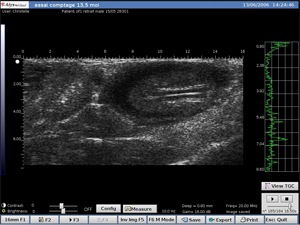

Le DERMCUP est équipé d’une sonde 25 MHz.

Il permet d’acquérir, de façon non-invasive, des coupes verticales in vivo: 16 mm x 12 mm.

• Détection précoce de tumeurs

• Suivi de l’évolution des tumeurs

Rein